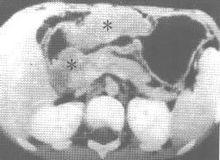

3.超聲內鏡檢查(endoscopic ultrasongraphy) 通過超聲內鏡可清楚顯示胃壁各層組織,從而可見胃淋巴瘤之浸潤情況該技術對上消化道惡性腫瘤之檢查可達83%的敏感率及87%的陽性率。同時可明確胃周淋巴結轉移情況。

4.灰階超聲和CT檢查 可見胃壁呈結節狀增厚可確定病變的部位範圍以及對治療的反應。表現為腹部腫塊的胃淋巴瘤,超聲檢查可助診斷。